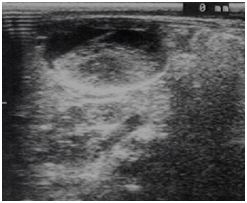

We report the case of a 28 days old girl with an antenatal diagnosis of abdominal mass. The physical examination was negative, blood sample results were within normal ranges (alpha-fetoprotein, bHCG and CA125). Urinalysis showed a small amounts of blood cells and leucocyturia, whereas the urine culture was positive for Escherichia coli (105). A micturitional cystourethrography and a complete abdominal ultrasound were performed. The micturitional cystourethrography showed a normal bladder for size and localization, with a lateral deflection of bladder imaging due to mass compression (Figure 1). The abdominal sonography showed a roundish mass with linear and exogenous margins, located in an anteromedian position compared to both the lower pole of the right kidney and the sub hepatic region. The mass was about 4x3x3 cm, and had a mixed solid -liquid echo structure (Figure 2) (Figure 3). A CT scan confirmed the presence of a 4cm cystic formation in the hepatic region but a subsequent MRI showed the mass in the right iliac fossa, and ruled out the involvement of other organs. In order to define a correct diagnosis and the subsequent surgical strategy we decided to perform a laparoscopic exploration. It was possible to identify a cystic mass in the sub-hepatic space with a diameter of 3-5cm. The mass was mobile, well delimited by the surrounding organs, with a thin long vascular pedicle (Figure 4). The exploration of the abdomen was normal and the left sided ovary and fallopian tube were normal. Although the diagnostic tests were negative, to completely rule out a neoplastic formation, the mass was totally removed through a minimal laparotomy to avoid dissemination of the fluid within the abdominal cavity in case of cyst rupture, according to the uncertain nature of che cyst. The histological diagnosis was “self amputated ovarian cyst” with necrosis and hemorrhagic fluid inside. The postoperative period was regular and the patient discharged on the second day after surgery.

Figure 1 N=57; Epidemiological distribution of the pathological fractures, traumatic fractures, and nonunion.